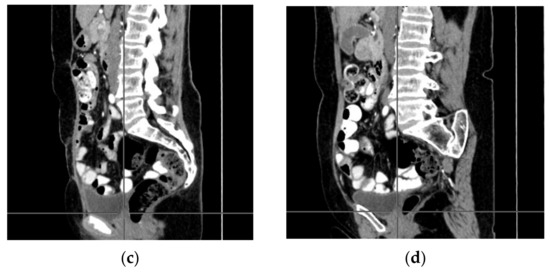

A computer tomography of the abdomen and pelvis was also performed every 3 months for the possible detection of ovarian cancer recurrence. No CT changes suggestive of recurrence were observed in the patient during the treatment. There are illustrates scans on the same section from CT performed at the beginning of PARP inhibitor treatment (Figure 2) and before 48 cycle of olaparib chemotherapy (Figure 3).

Figure 2.

(a–d) CT scans performed at the beginning of olaparib treatment.